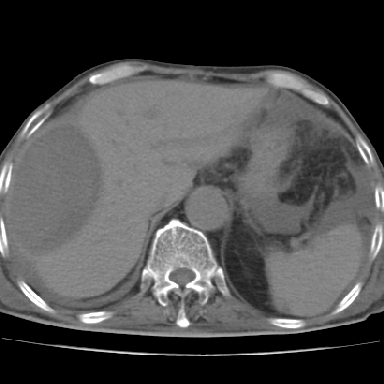

以下是引用qian在2006-12-4 19:11:00的发言:[br]胸腔和腹腔内均见有液性影,肝上极包膜下有一较大椭圆形低密度影,密度均匀,边缘清晰,结合病史考虑术后肝脓肿并胸腹腔积液。

以下是引用dyqct在2006-12-4 19:54:00的发言:[br]考虑:1、肝包膜下脓肿;[br] 2、少量腹水;[br] 3、右侧少量胸膜腔积液。